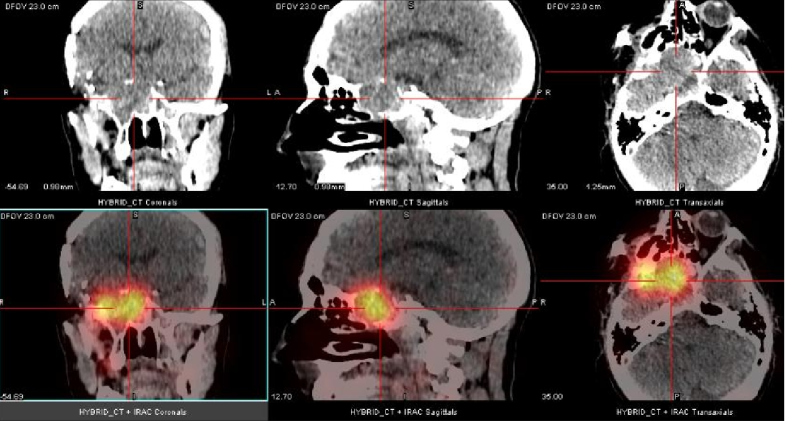

Uma quarta recorrência foi identificada por RM na região retro-orbital direita com progressão ipsilateral anterior para lobo temporal após cinco anos. Investigação pré-operatória constatou uma massa pulmonar na parte inferior do lobo superior esquerdo. Biópsia guiada por CT evidenciou meningioma atípico grau II. Um estudo com 111In-Oct SPECT/CT foi realizado como extensão diagnóstica. Foi evidenciada intensa fixação do 111In-Oct associada à presença de receptores de somatostatina a nível da lesão pulmonar (fig. 1), assim como na lesão temporal direita (fig. 2), confirmando recorrência. Tambén foi detectada fixação linfonodal direita (fig. 3).